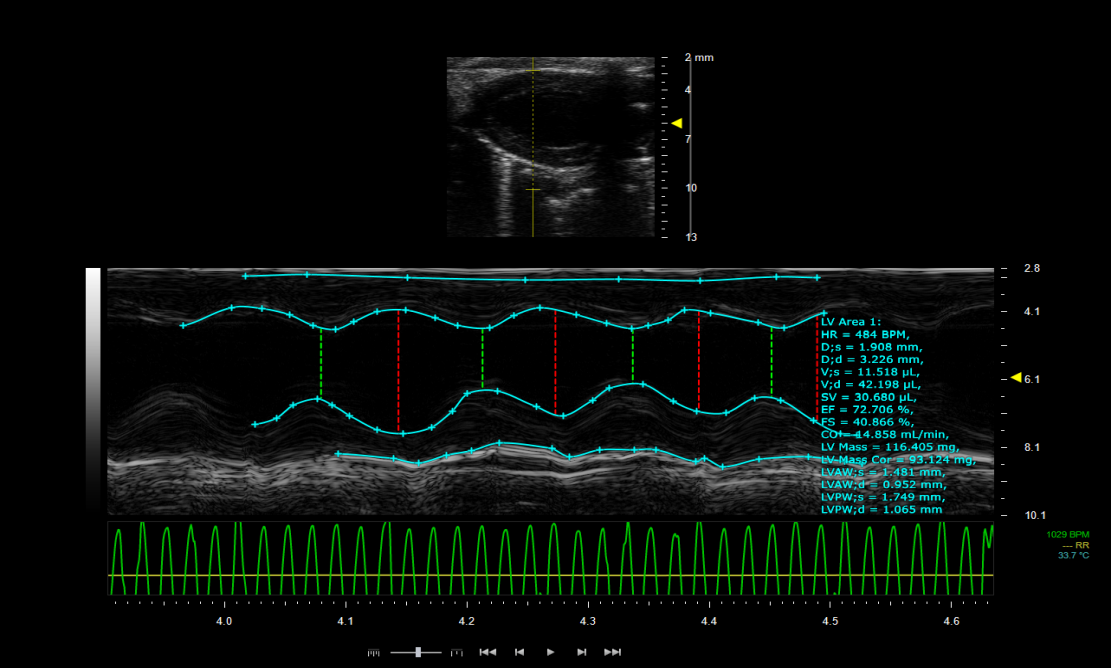

⑤ LV Trace自动分析功能,轻松获取高阶的心功能评估

超声系统成像范围广,适合对软组织脏器、病变组织等进行观察和测量,但对肺成像困难。Visual sonic Vevo3100型超高分辨率小动物超声成像系统带有小鼠专用心电监测系统,在采集超声信号的同时记录小鼠心电信息,配合仪器的多普勒功能,不仅能够测量心室壁厚度等参数,还能够测量血流速度、射血分数、心室容积等反映心脏功能的参数。